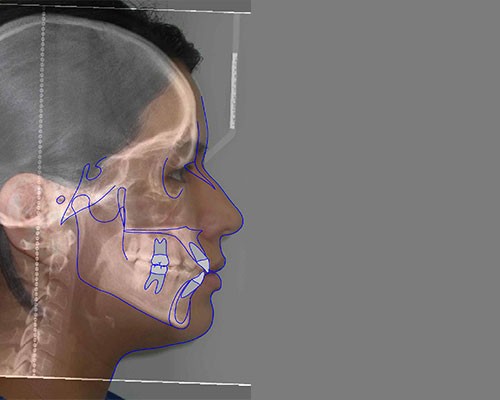

SISTEMAS DIGITALES 3D